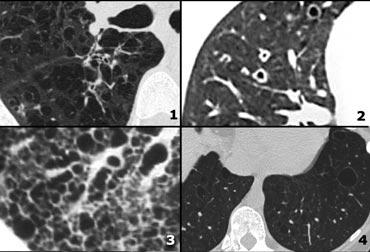

Honeycombing

Tổ ong được định nghĩa bởi sự hiện diện của các khoang nang nhỏ với thành dày không đều được cấu tạo bởi mô xơ.

Các nang tổ ong thường chiếm ưu thế ở vùng phổi ngoại vi và dưới màng phổi bất kể nguyên nhân của chúng.

Các nang tổ ong dưới màng phổi thường xuất hiện theo nhiều lớp liên tiếp.

Đặc điểm này có thể giúp phân biệt tổ ong với khí phế thũng cạnh vách ngăn, trong đó các nang dưới màng phổi thường chỉ xuất hiện theo một lớp duy nhất.

Trường hợp bên trái cho thấy các nang tổ ong dưới màng phổi ở nhiều lớp liên tiếp.

Ngoài ra còn có sự chiếm ưu thế ở thùy dưới và giãn phế quản do co kéo lan rộng.

Những phát hiện này điển hình cho Viêm phổi Mô kẽ Thông thường (UIP).

UIP hay ‘phổi giai đoạn cuối’ là một chẩn đoán bệnh lý và thường được xác định qua sinh thiết phổi, khi hình ảnh tổ ong có thể nhìn thấy được.

Xơ phổi vô căn (IPF) chiếm hơn 60% các trường hợp UIP.

UIP kèm xơ hóa phổi cũng là một dạng tổn thương phổ biến trong bệnh tự miễn và tổn thương phổi do thuốc.

Nhiều loại thuốc đã được xác định có liên quan, nhưng dạng tổn thương này thường gặp nhất là do các thuốc hóa trị liệu gây độc tế bào như bleomycin, busulfan, vincristine, methotrexate, adriamycin và carmustine (BCNU).

Bên trái là một trường hợp khác của UIP.

Sự chiếm ưu thế ở vùng phổi dưới được thể hiện khi bạn cuộn qua các hình ảnh.

Lưu ý độ mờ kính mài ở thùy dưới phổi trái do mô xơ thay thế không khí trong các phế nang.